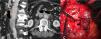

La angiografía computarizada multifásica (angio-TC) es de elección en situaciones de urgencia, permitiendo una evaluación detallada de las estructuras vasculares. La resonancia magnética, la ecografía y las técnicas de medicina nuclear pueden ser útiles en ciertos casos.

Los signos directos en angio-TC incluyen la visualización del tracto fistuloso y la extravasación de contraste, no obstante, es más frecuente identificar signos indirectos como anormalidades de la pared aórtica, engrosamiento de la grasa perivascular o colecciones. Además, hay ciertas condiciones que pueden imitar a las fístulas, lo que hace esencial un diagnóstico diferencial.

Multiphasic computed tomography angiography (CTA) is the gold standard in emergency situations, enabling a detailed evaluation of vascular structures. Magnetic resonance imaging, ultrasound and nuclear medicine techniques may be useful in certain cases.

Direct signs in CTA include visualisation of the fistulous tract and contrast extravasation. However, it is more common to identify indirect signs such as aortic wall abnormalities, perivascular fat thickening or collections. In addition, other conditions can mimic fistulae, making a differential diagnosis essential.